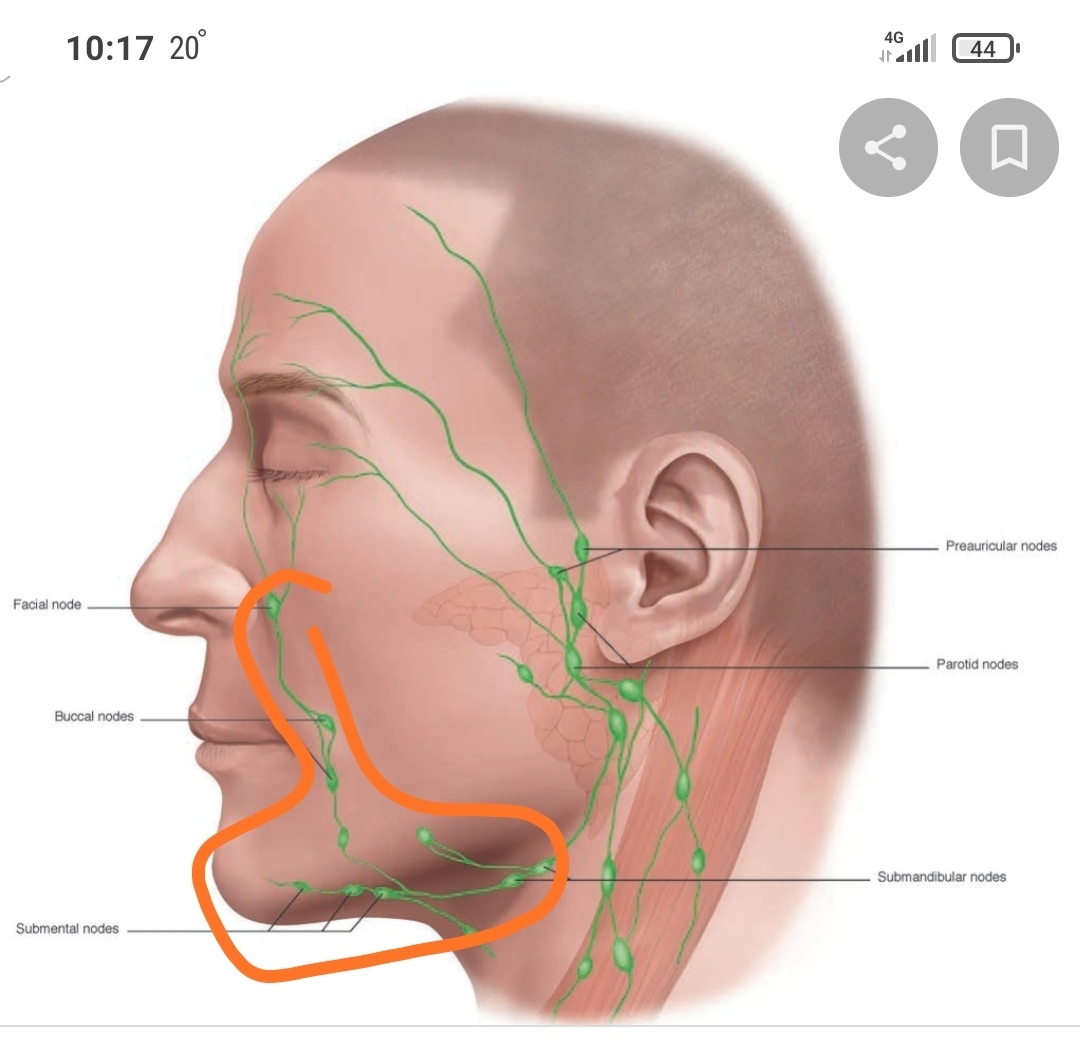

Изображения и схемы: как выглядит лимфа